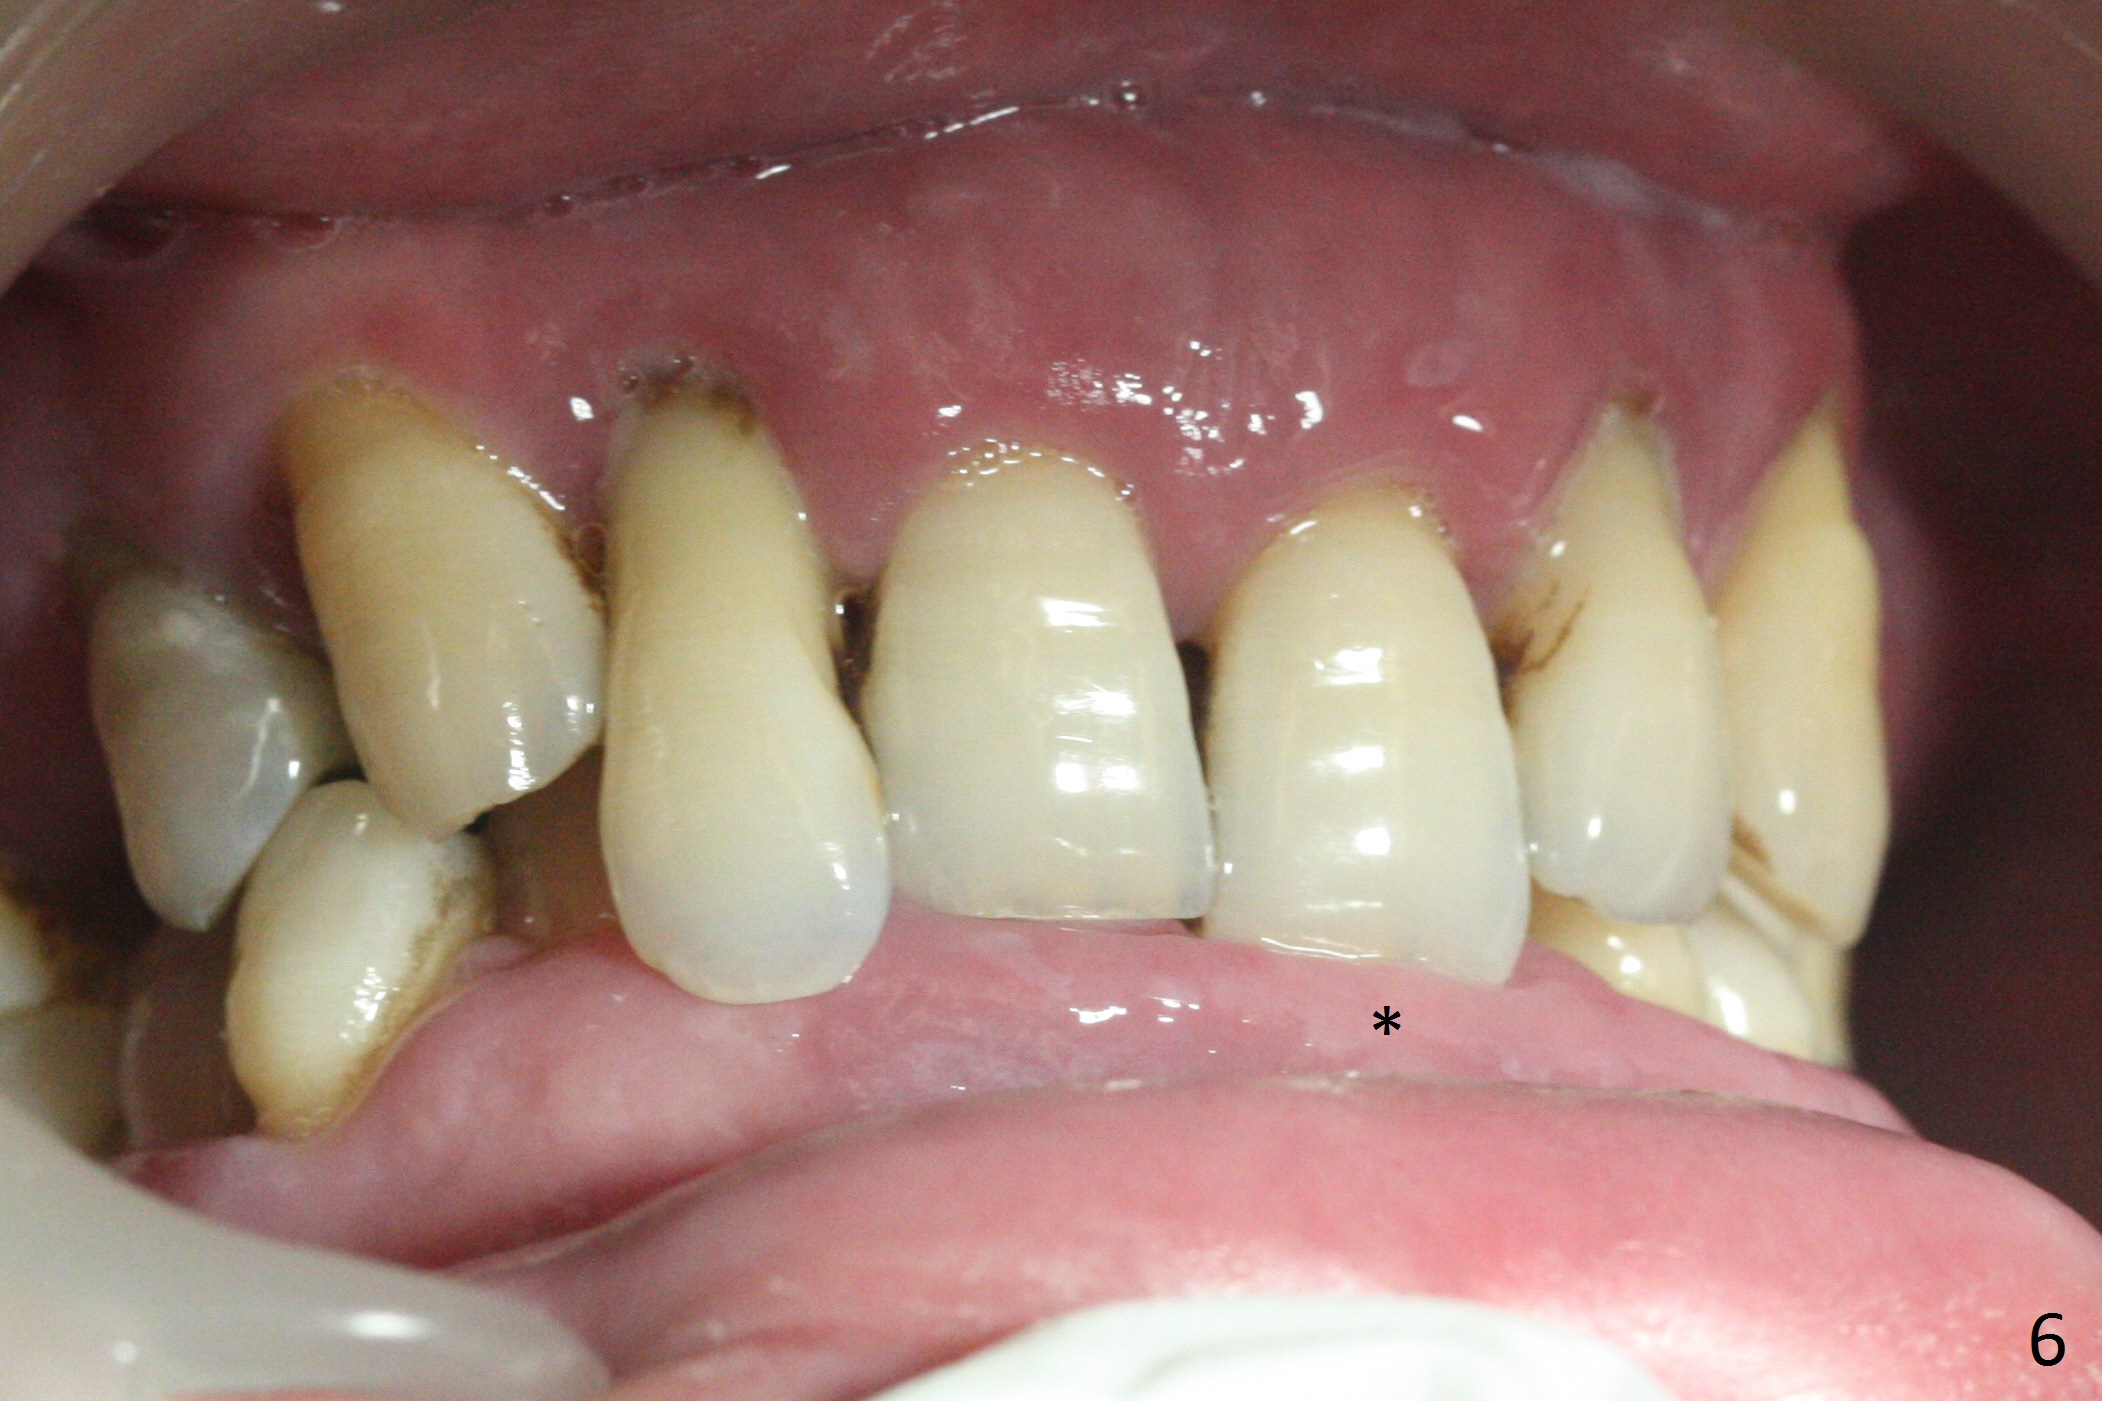

A 36-year-old man (ex-smoker) has advanced chronic periodontitis (Fig.1-5). His chief complaint is "I cannot chew on the right side now because of pain (Fig.1: #3 abscess <) and the bottom front teeth are loose (Fig.2,5: #23-26)". He has not masticated on the left side because of the mobile teeth. Due to finance, implants will be placed at #3,4 (Fig.12), 23 and 26 at the appointments of scaling & root planing.

Class II Division II malocclusion (Fig.2,6) will make it difficult to restore #23-26 implant-supported FPD. Although the teeth #7-10 may need to be replaced later (Fig.7,8), enameloplasty will be conducted for #7-10 (Fig.9 white area; Fig.12 black circles (gross reduction)) prior to #23-26 extraction and implant placement (Fig.10). To be flexible in restoration (angulation) and possible future hybrid denture, 2-piece narrow implants will be placed (3.0 or 3.3 mm) instead of 1-piece ones. In fact CBCT shows that the narrowest regular implant (3.8 mm) can be placed in the lower anterior region (Fig.13-15).